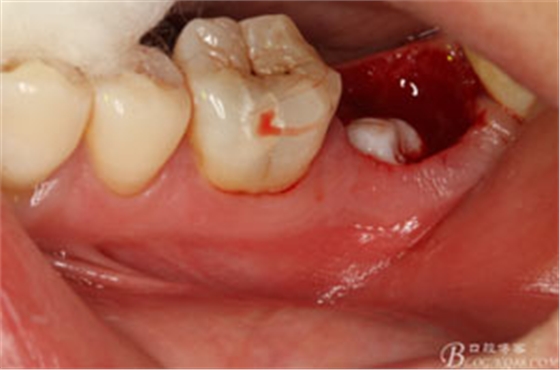

圖9.清理牙槽窩過(guò)后。多生牙的牙冠暴露在牙槽窩內(nèi)。